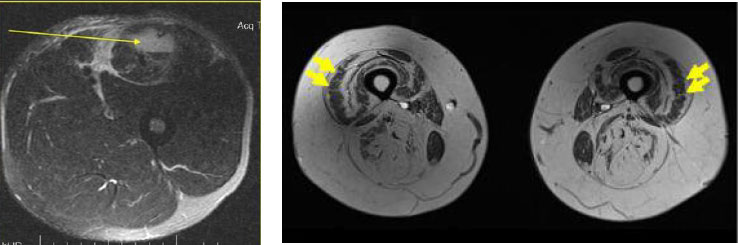

Причина № 2: Тонус мышц ног – хорошо развита сосудистая сеть в ногах – корректный венозный отток, хорошая капилляризация мышц ног – здоровье сердечной мышцы и системы кровообращения. Заметьте, что при упоминании здоровой сердечно-сосудистой системы просто необходимо иметь тренированные ноги. Ноги – это почти 50 % сосудов в теле человека. При отсутствии нормального тонуса в ногах начинается жировая дистрофия мышц (замена части мышечных волокон жировыми клетками). Мышцы приобретают черты Мраморного мяса.

Посмотрите на срез бедра, который сделан с помощью МРТ.

Слева – нормальная, тонусная мускулатура в бедре, справа – жировое перерождение мышц (мышцы просто отсутствуют). Нормального кровообращения в таких мышцах просто не будет, так как мышц нет. Скорее всего будет варикоз. Жировая мышечная дистрофия не редкость, когда речь идет о полном отсутствии нагрузки (она должна быть!) на скелетную мускулатуру.